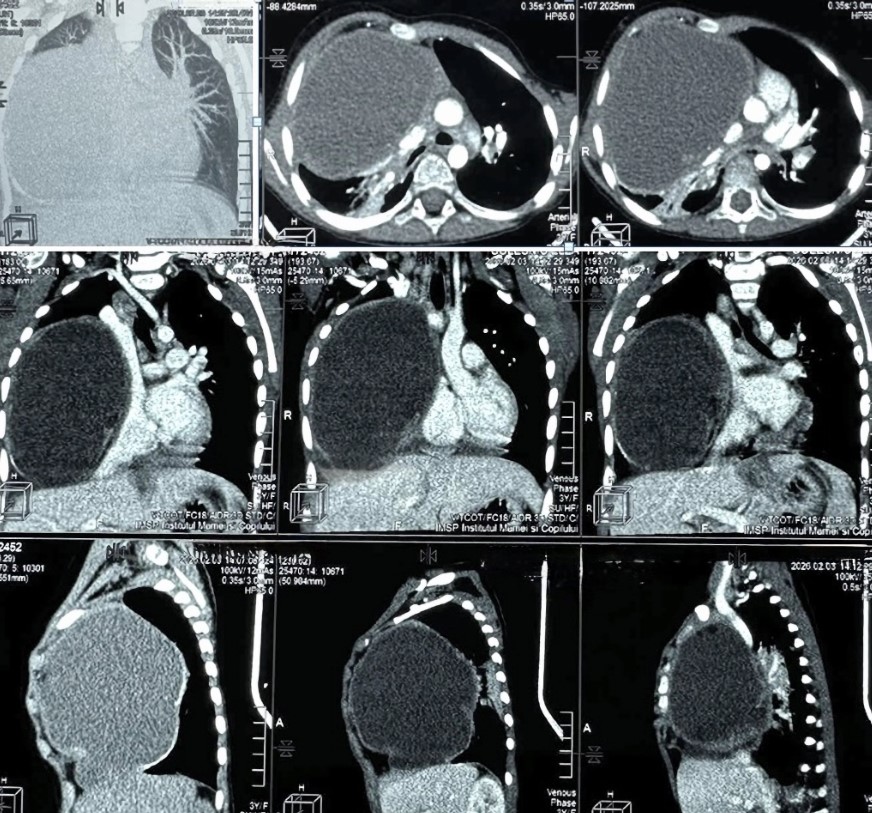

Опухоль размером примерно 12 × 9 × 10 сантиметров занимала около 80% области грудной клетки. Фото Центра детской хирургии им. Н. Георгиу